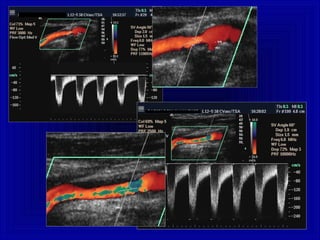

Aliasing in Vaso Normale:Aliasing in Vaso Normale:

Distribuzione regolare , dal centro alla periferia dei pixelDistribuzione regolare , dal centro alla periferia dei pixel

Aliasing in Stenosi:Aliasing in Stenosi:

Distribuzione irregolare , aDistribuzione irregolare , a “mosaico” dei pixel“mosaico” dei pixel

turbolenza

V 200%

flusso “prestenotico”

a velocità ridotta

accelerazione + jet

alla stenosi

“poststenotica”

Aliasing e Stenosi